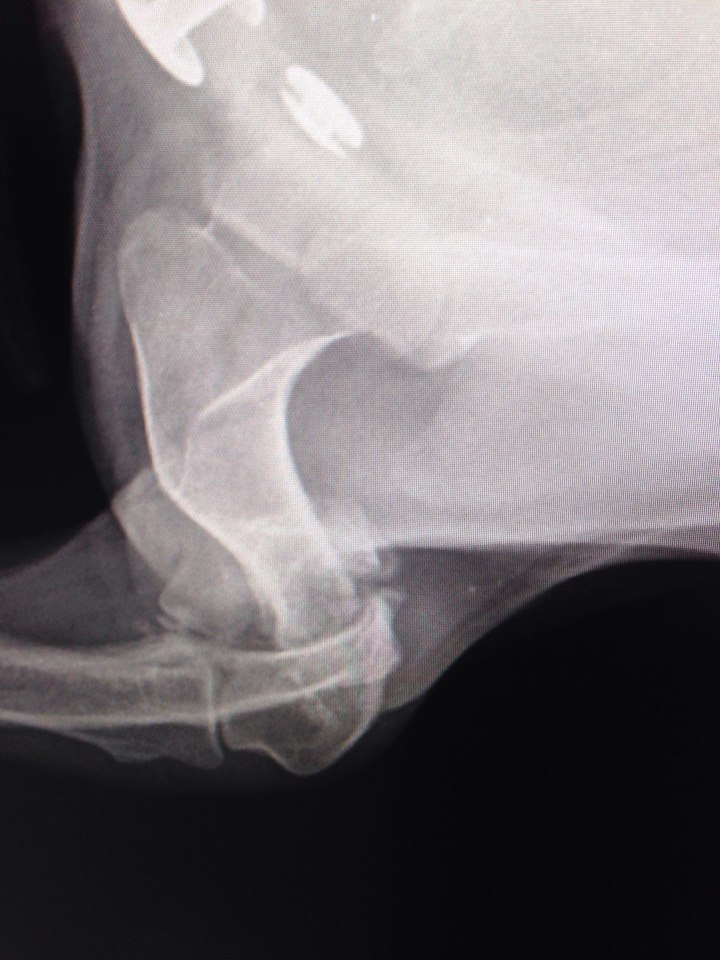

Надо мелкой рентген срочно делать

На лапу не наступает.... гипс не помню сколько был, но возможно, не правильно сложили

Вобщем все гораздо хуже оказалось.Только характер приятный,ласкавая.

Очень паршивый перелом.... сложная операция.

Не понятно куда и зачем одевали гипс.... зато стерилизовали.

Да,так и есть.Пишу посты,кидаю в личку-дорого обходятся чужие ошибки.Самое обидное,что если бы сразу сделали,то даже не хромала бы и цена была бы совсем другая.